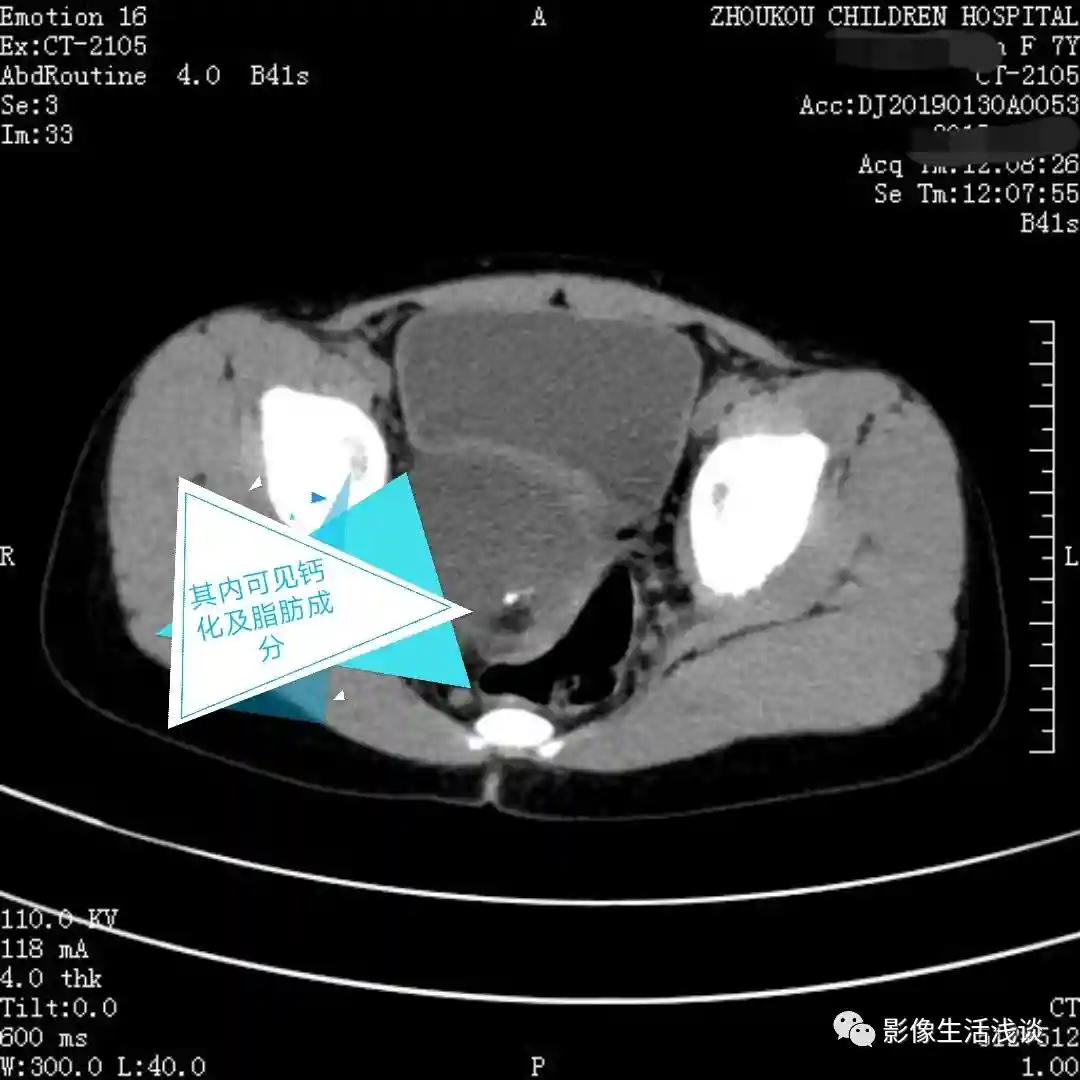

第二个病例女性63岁,体检CT中发现盆腔内左附件区囊性占位: